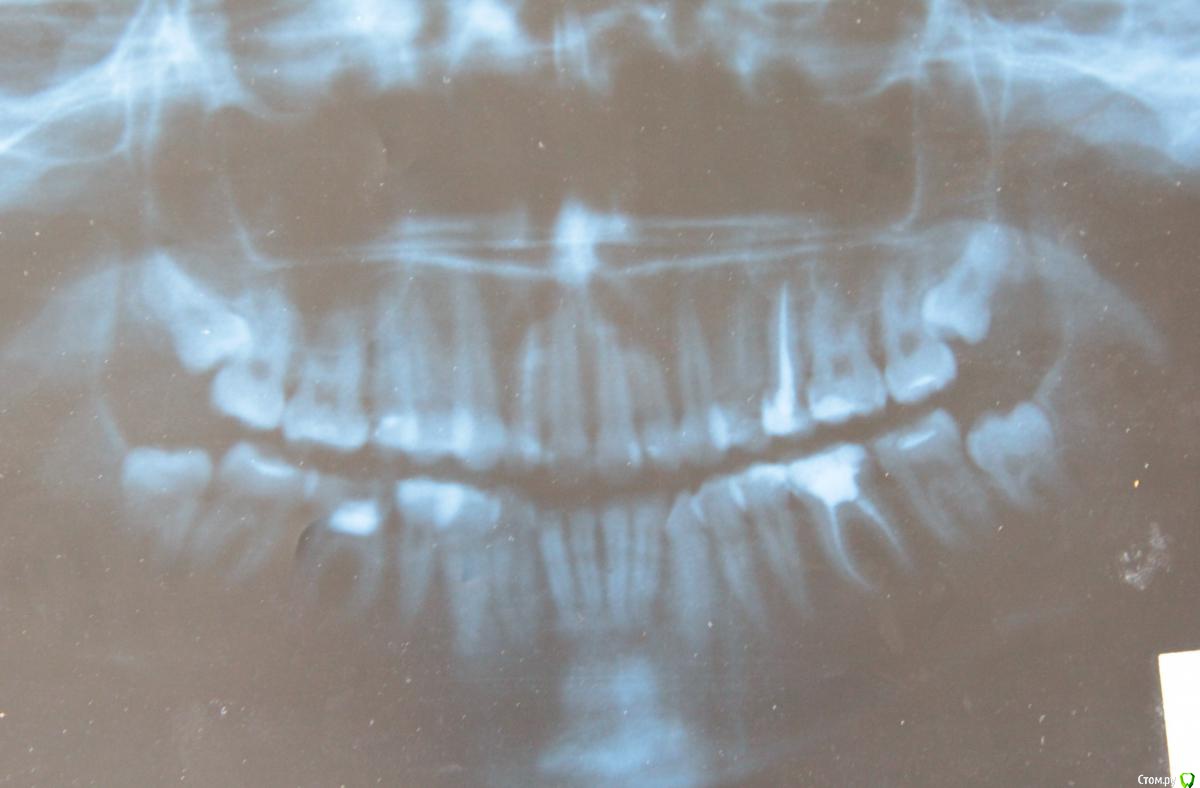

holden777 Опубликовано 11 июня, 2015 Поделиться Опубликовано 11 июня, 2015 (изменено) Добрый день всем! Очень надеюсь на советы профессионалов и их помощь!В 2012 году у меня началось оседание десны. Первые 1,5 года бегала по врачам, сдавала анализы, терапевты твердили, что это авитоминоз и сниженный иммунитет. В течении этого времени 3ка снизу очень искривилась. Слава богу,попался толковый специалист и сказал мне обратиться к ортодонту. Тут все и началось. Была у нескольких специалистов, никак не могу решиться, что мне лучше всего сделать. 1 - один специалист (лучший ортодонт в городе) советует удалить верхние зубы мудрости, снизу удалить 6-ки, они у меня мертвые. Далее поставить две системы самолигирующих брекетов. 2 - второй специалист советует снизу удалить 6-ки, а вверху - или зубы мудрости или 4ки. Далее - носить каппу сначала. Если не поможет, то брекеты.У меня несколько вопросов.1. Если удалить зубы мудрости и верхние и нижние, прекратится ли оседание десны и искривление зубов?2. Обязательно ли ставить брекеты? В эстетическом смысле меня устраивает, как выглядят зубы. Но специалист 1 говорит, что зубы надо обязательно растянуть,чтобы снять с них нагрузку, т.к. зубы мудрости их толкают в кучу.3. Вылезут ли зубы мудрости снизу, если удалить 6ки? Ведь там останется большой промежуток. Какова вероятность того, что промежуток закроется?4. При использовании брекетов не станет ли десна еще больше оседать? Не появятся ли промежутки между зубами?Очень прошу вашей помощи. За постановку брекетов и лечение нужно отдать немалые деньги. Я хочу быть уверена в том, что это действительно необходимо и без этого лечения нельзя обойтись. Просто хочу знать, достаточно ли будет просто удалить лишние зубы, которые способствуют искривлению других зубов и оседанию десны?Буду ждать ваших откликов, ребята!Если нужно сделать дополнительные фотографии, я сделаю. Снимок панорамный сделан год назад. В конце июня мне исполнится 26 лет. Изменено 11 июня, 2015 пользователем holden777 Ссылка на комментарий

holden777 Опубликовано 11 июня, 2015 Автор Поделиться Опубликовано 11 июня, 2015 Фотографии: Ссылка на комментарий